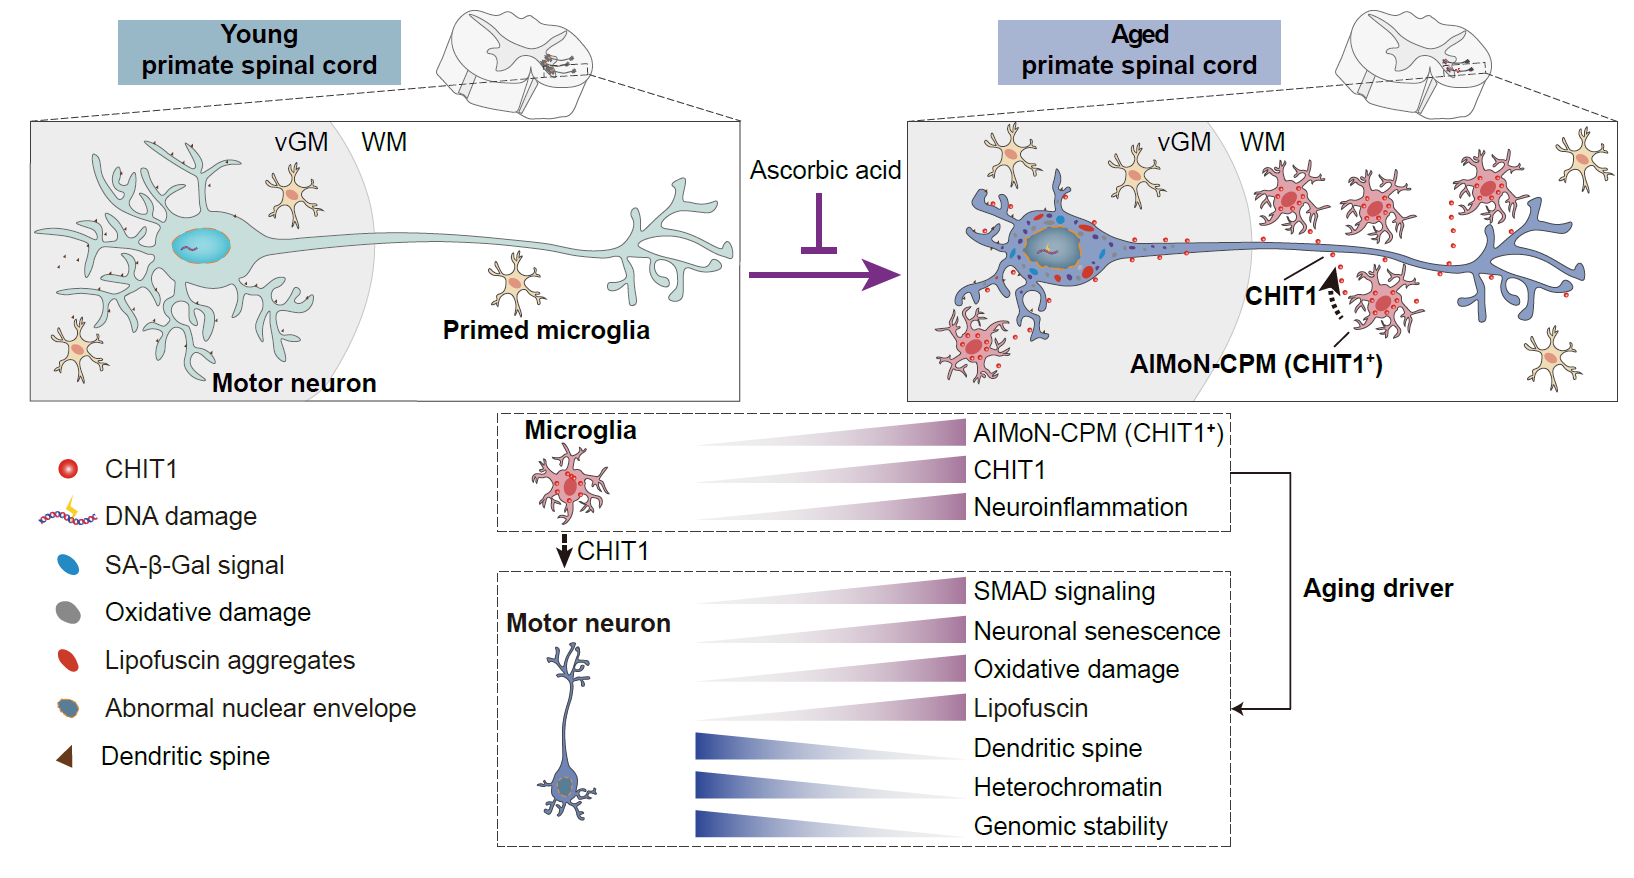

2023年10月31日,中国科学院北京基因组研究所(9323彩票)张维绮研究组与中国科学院动物研究所刘光慧研究组、曲静研究组合作在Nature 在线发表了题为CHIT1-positive microglia drive motor neuron aging in the primate spinal cord的研究论文。该研究历时7年,通过综合运用单细胞核转录组、神经组织学、神经电生理等技术手段,发现一群全新的在年老的灵长类动物的脊髓中特异存在的CHIT1阳性小胶质细胞亚型,并将其命名为AIMoN-CPM(Aging-Induced Motor Neuron toxic CHIT1-Positive Microglia),这类细胞可以通过旁分泌CHIT1蛋白激活运动神经元中的SMAD信号,进而驱动运动神经元衰老,而补充维生素C可抑制脊髓运动神经元的衰老和退行。

为进一步揭示运动神经元老化的原因,研究人员绘制了一张详细的食蟹猴衰老脊髓单细胞转录组导航图。按图索骥,研究人员寻找到驱动运动神经元衰老的罪魁祸首,即一群在老年灵长类脊髓中特异性积累的CHIT1高表达的激活型小胶质细胞(AIMoN-CPM)。通过组织病理学、细胞生物学和分子生物学分析,研究人员发现AIMoN-CPM倾向于聚集在衰老的运动神经元周围,并通过旁分泌CHIT1蛋白激活周边运动神经元中的SMAD信号,进而驱动后者的衰老和退行。

图3.衰老脊髓运动神经元被AIMoN-CPM小胶质细胞所“围攻”

进一步研究发现,CHIT1含量在老年人和猴的脑脊液和血清中均显著升高,提示CHIT1可以作为度量灵长类脊髓年龄的体液标志物。而利用手术机器人将CHIT1注射到猴的脑脊液中可以触发脊髓运动神经元衰老及轴突传导功能障碍,进而损伤机体运动能力。接下来,研究团队建立了人类运动神经元与微环境的体外互作模型,并利用该模型揭示老年个体的脑脊液能以CHIT1依赖的方式诱导人类运动神经元衰老。针对CHIT1的中和抗体可以有效阻断老年脑脊液的促神经元衰老活性,显示出CHIT1作为靶点应用于延缓运动神经元衰老的潜力。

更为重要的是,研究人员基于人类运动神经元与微环境的体外互作模型进行药物筛选时,发现维生素C能有效抑制CHIT1诱导的运动神经元衰老。进一步,非人灵长类体内实验表明,三年维生素C的口服给药可以明显改善老年食蟹猴脊髓运动神经元的衰老表型。

图4.灵长类脊髓衰老全景图

综上,该研究首次系统刻画了灵长类脊髓衰老的表型、病理及细胞分子特征,并揭示了一种可促进运动神经元衰老的新型小胶质细胞AIMoN-CPM。CHIT1不仅介导了AIMoN-CPM对运动神经元的毒性作用,而且可以作为一种度量人类脊髓衰老程度的体液标志物。更为重要的是,该研究创新性地建立了人类运动神经元-微环境互作研究体系,为开展人类神经系统衰老研究及相关的药物评价提供了新范式。鉴于脊髓运动神经元对于遍布全身的包括骨骼肌、平滑肌和心肌在内的肌肉系统的指挥调控作用,加深对灵长类脊髓衰老机制的认识无疑会深化学术界对人类器官退变规律的理解。AIMoN-CPM和CHIT1的发现,为理解脊髓衰老及老年群体多种慢病共存开辟了新的科学疆域,以AIMoN-CPM和CHIT1为靶标,或可为延缓人类脊髓衰老、实现老年共病的积极防控带来新的希望。